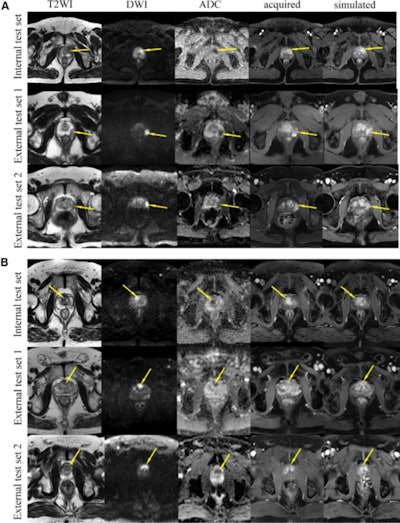

Axial prostate MRI scans. The simulated contrast-enhanced axial prostate images were comparable with the acquired contrast-enhanced images. Example images from the internal test set and the two external test sets show (A) a lesion in the peripheral zone (arrows) and (B) a lesion in the transition zone (arrows). Notably, there are visual differences between the simulated and acquired contrast-enhanced images regarding the degree of lesion enhancement and the measurement of lesion size (see Fig S4). ADC = apparent diffusion coefficient, DWI = diffusion-weighted imaging, T2WI = T2-weighted imaging. Images and caption courtesy of the RSNA.

Huang's group found that the simulated and acquired contrast-enhanced images were comparable as calculated by the multiscale structural similarity index (which measures the quality of images and videos, with 1 as reference), showing values of 0.82 for the internal test set, 0.71 for external test set one, and 0.69 for external test set two.